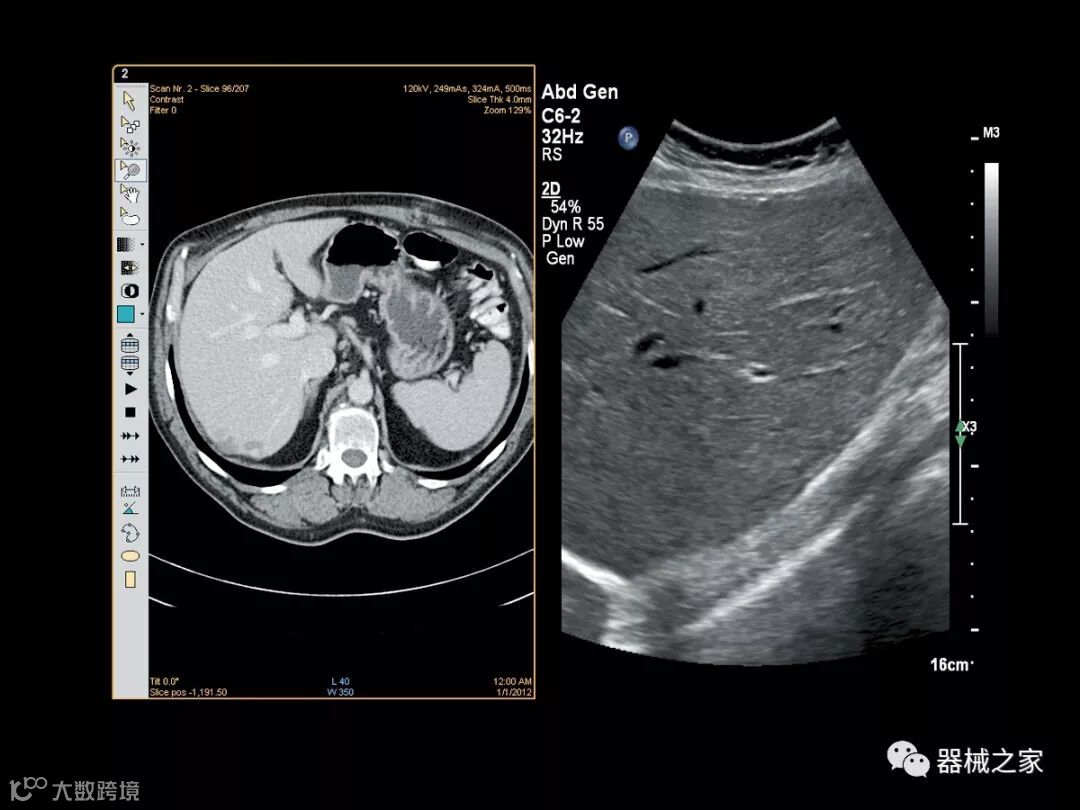

Baptist Health South Florida成为去年秋天西门子医疗保健公司Acuson Sequoia的首个商业安装网站。该系统将有助于增强胃肠病学,初级保健和减肥专业的成像能力。Sequoia可实现高分辨率成像,自动适应患者的体型和个人身体特征,有助于更加自信的诊断。它适应患者的组织密度,刚度和超声波束吸收的生物声学变化。这使得系统可以穿透高达40厘米而不会因衰减回波信号而导致图像质量下降。